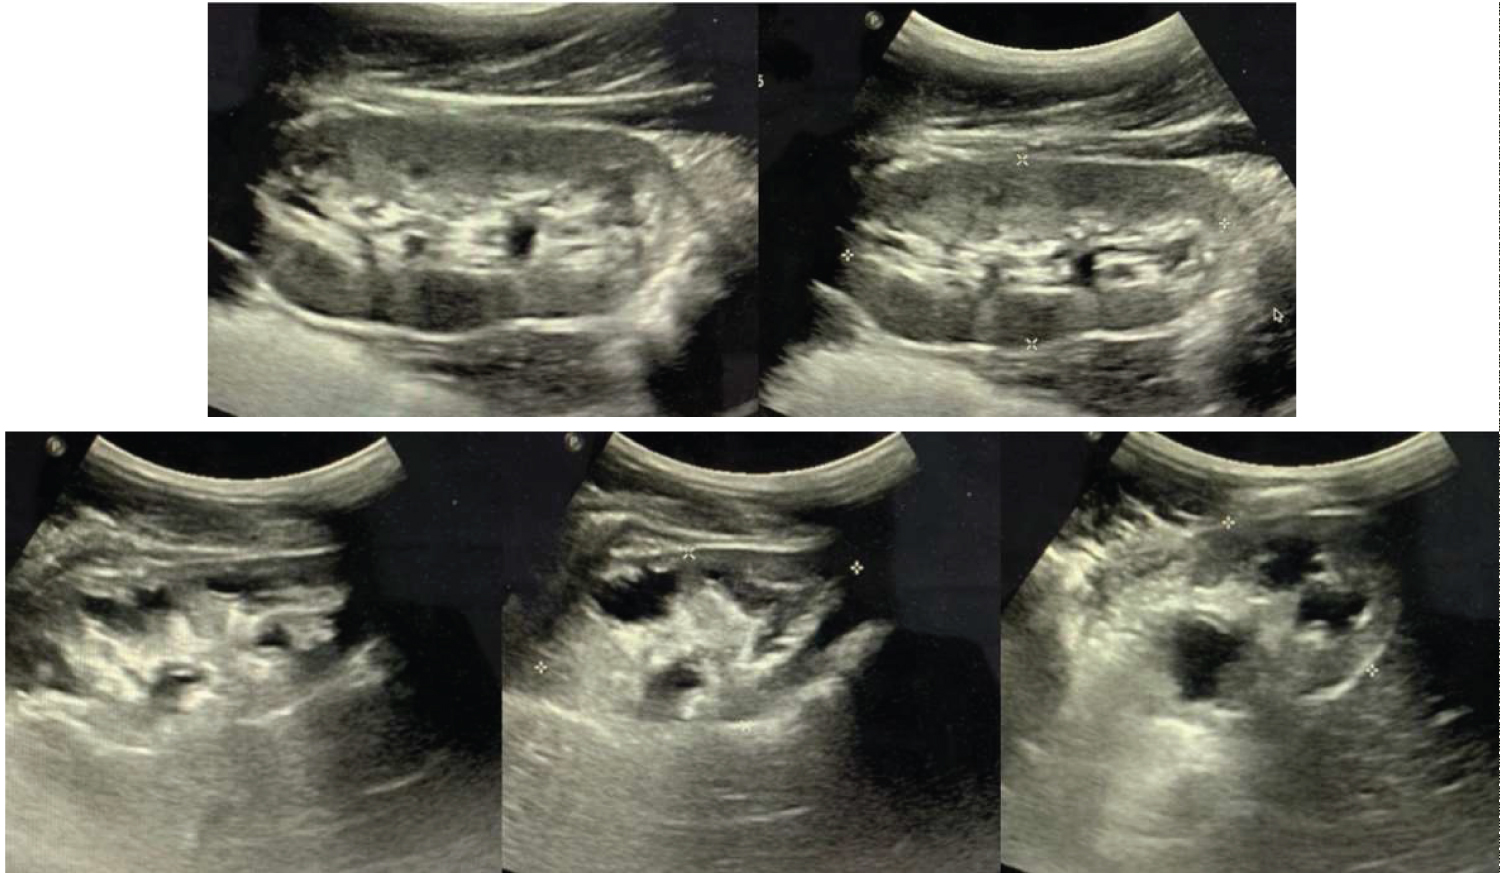

Because of the urinalysis suggesting a urinary tract infection in a male patient and the low weight, a kidney, ureter and bladder ultrasound was ordered to look for any anatomical or structural abnormalities (Figure 1). Further, before the vesicoureteral reflux diagnosis was clear, the patient was treated for a presumed urinary tract infection with PO amoxicillin/clavulanate for 5 days.

Figure 1: Kidney ultrasound demonstrating hydronephrosis and collecting system dilation of the right kidney (bottom images). The left kidney (top images), was also reported with hydronephrosis but does not show collecting system dilation. View Figure 1

The ultrasound reported bilateral hydronephrosis. The right kidney measured 59 × 33 × 35 mm, with a volume of 37.1 ml, with loss of the sinus-parenchymal relation due to collecting system dilation extending to the renal pelvis and chalices, compressing the renal parenchyma.

The left kidney measured 72 × 35 × 32 mm, a volume of 72.8 ml, with preserved medulla-cortex and sinus-parenchymal relation. Cortex measured 6 mm. No evidence of collecting system dilation was reported. The bladder was described in its usual form and location, with regular, defined borders, a 276 ml volume and 1 mm thickness. Postmictional volume was 110.2 ml, with a 39.9% of urinary residual volume. Bilateral ureteral dilation, with right side predominance was reported.